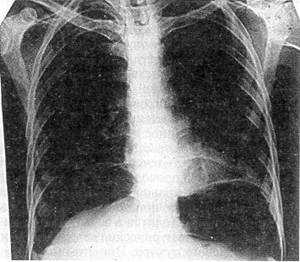

Практически всем пострадавшим должна выполняться обзорная рентгенография живота, а при необходимости — и других анатомических областей При тяжелом состоянии пострадавшего исследование проводится в реанимационном отделении или на операционном столе; обязательно обзорное исследование грудной и брюшной полостей при горизонтальном положении больного; при необходимости делается еще снимок в латеропозиции — на здоровом боку. Этот доступный, неинвазивный метод исследования позволяет не только выявить воздух в свободной брюшной полости (рис. 30), но и при приобретении навыков чтения снимков распознать внутрибрюшное кровотечение: уровни жидкости, симптом «всплывания» кишечника При повреждении печени отмечаются нечеткость нижнего края органа из-за наличия сгустков крови в подпеченочном пространстве, высокое стояние правой половины диафрагмы и даже расширение и гомогенное затемнение правого латерального канала Сходные изменения выявляются при травме селезенки, но уже слева Образование периспленальной гематомы вызывает смещение пнев-матизированного желудка вправо и вниз (М К Щербатенко и соавт, 1975, 1986) О наличии забрюшинной гематомы свидетельствует гомогенное плотное затемнение соответствующей стороны при отсутствии четкости контуров почки и поясничной мышцы (рис 31) Патогномоничным симптомом разрыва забрюшинного отдела двенадцатиперстной кишки является картина ретропневмопе-ритонеума — забрюшинной «эмфиземы» (рис 32) Обзорная рентгенография позволяет выявить разрыв диафрагмы и смещение органов

Рис 33 Обзорная рентгенограмма груди и живота больного И , 29 лет, с сочетанной закрытой травмой груди и живота видна деформация левой половины грудной клетки вследствие переломов ребер, разрыв диафрагмы — желудок и петли

кишечника в плевральной полости, органы средостения смещены вправо

брюшной полости в плевральную, что более наглядно при разрыве левого купола диафрагмы (рис. 33).